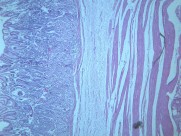

本病以胃粘膜萎缩变薄,粘膜腺体减少或消失,并伴有肠上皮化生,固有膜内多量淋巴细胞、浆细胞浸润为特点。本性胃炎的病因比较复杂,部分可能与吸烟酗酒和用药不量有关,部分由慢性浅表性胃炎迁移发展而来,还有部分属兔自身免疫疾病。